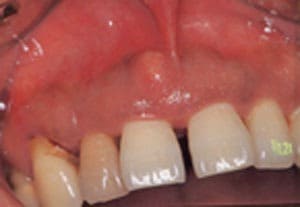

②歯周炎由来による歯周膿瘍

これに対して、歯の横に膿がたまる場合の多くは歯肉と歯周組織(歯周病)が原因で起こることがあります。